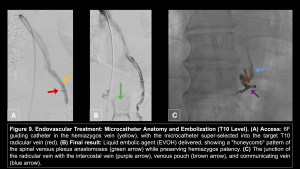

Once the fistula is localized, transvenous embolization with liquid embolic agents (e.g., Onyx/EVOH) offers a minimally invasive alternative to surgical ligation. The goal is to occlude the connection between the venous pouch and the paraspinal vein while preserving the drainage of the spinal cord.

Outcomes and Follow-up

Successful occlusion is defined by the penetration of the embolic agent into the proximal radicular vein and the adjacent internal vertebral venous plexus. Post-procedural imaging confirms the stability of the embolic cast.